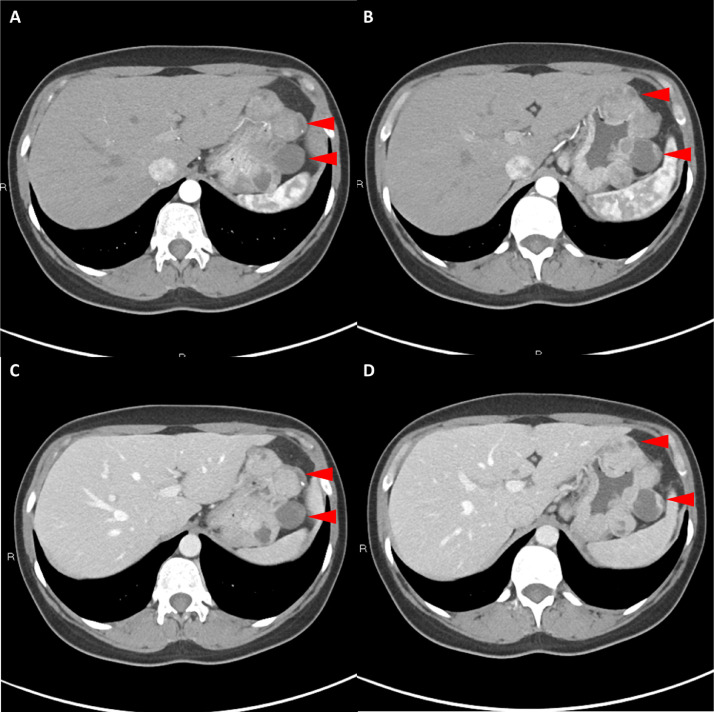

Fig. 4

圖 4: 胃腸道間質(zhì)瘤的三維表示。 (A 和 B)胃腸道間質(zhì)瘤在動脈期和冠狀面的 3D 可視化提供了進(jìn)一步的解剖細(xì)節(jié)和空間信息。